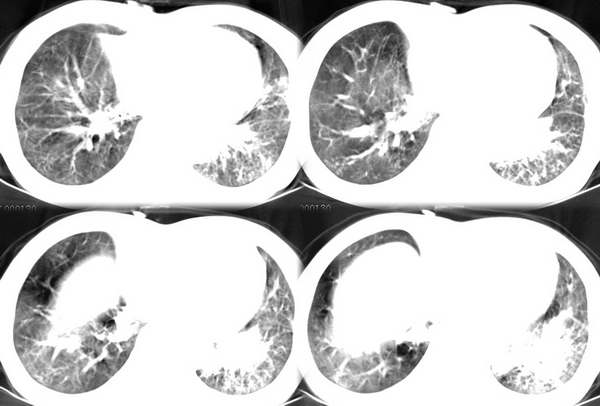

咳嗽6月低热1月!

右上肺和左下肺见有斑片状及条片状影,边缘模糊,纵隔内无肿大淋巴结,结合病史考虑肺结核可能大。

右上叶背段及左下叶见斑片状密度不均模糊影,右中叶支气管狭窄,中叶密度增高,体积缩小.纵隔未见明确淋巴结.结论:1、两俩结核,右中叶支气管内膜结核,并中叶肺不张。2、两肺炎;右中心型肺癌,并阻塞性肺不张。

右肺上叶尖后段及左肺舌叶 下叶见斑片状密度不均模糊影,右中叶支气管狭窄,中叶密度增高,体积缩小.纵隔未见明确淋巴结。考虑:双肺结核伴右侧中叶不张。

右上叶背段及左下叶见斑片状密度不均模糊影,右中叶支气管狭窄,近端未见肿块,中叶密度增高,体积缩小.纵隔未见明确淋巴结.结论:两肺结核,右中叶支气管内膜结核,并中叶肺不张。肺纹理粗乱,有慢支表现,伴有感染存在。

1.右下叶背段结核。2.支气管炎伴双下肺感染。3.右中叶内侧段肺不张。至于原因,考虑支气管内膜结核,建议纤支镜检查。

ct显示病灶呈多灶性分布,主要分布在双肺上叶后段,右肺中叶及左肺下叶,右肺上病灶内可见点状钙化,纵隔内示淋巴结钙化,结合病史6个月伴低热,考虑感染性病变,结核可能大.

右上叶及左下叶多发结节状、斑片状阴影。右中叶不张。支持肺结核并右中叶不张。